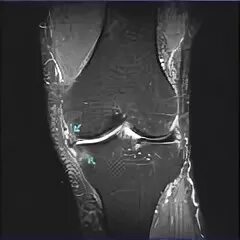

Дегенеративные изменения менисков stoller 1